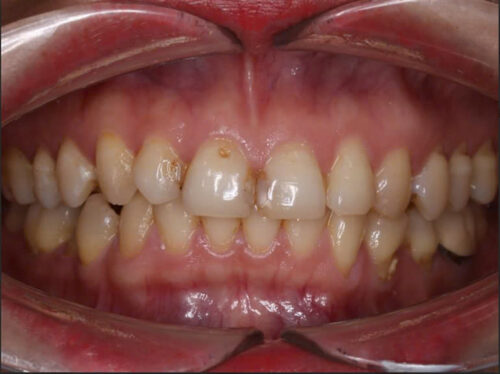

Hình 1: Bệnh nhân phụ nữ mang thai thường gặp nhiều vấn đề sức khỏe răng miệng

Trong thời gian mang thai, phụ nữ thường trải qua nhiều biến đổi về sức khỏe răng miệng do sự thay đổi hormone trong cơ thể. Theo Hiệp hội Nha sĩ Mỹ, khoảng 40% phụ nữ mang thai gặp phải các vấn đề như sâu răng, nhiễm trùng lợi, viêm lợi và viêm nha chu. Những vấn đề này có thể ảnh hưởng đến sức khỏe của thai nhi và tăng nguy cơ mắc các bệnh lý răng miệng trong tương lai. Chế độ ăn uống không lành mạnh và thói quen vệ sinh răng miệng không đúng cách có thể dẫn đến những vấn đề nghiêm trọng cho cả mẹ và bé. Vì vậy, chăm sóc răng miệng trong thời kỳ mang thai là rất cần thiết và cần được chú trọng.